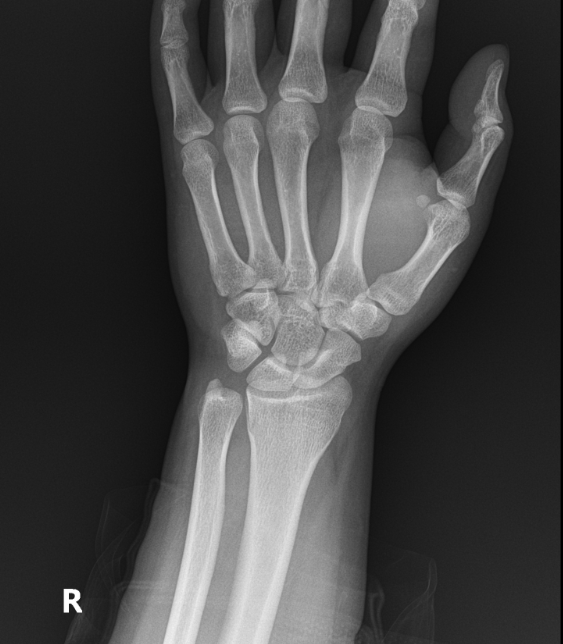

우측 손목 바깥쪽 척골 근처 통증으로 처음엔 힘줄염 진단받고 소염진통제 3개월 먹고 체외충격파 여러번 받았는데도 좋아지지 않아서 mri찍었습니다. mri상 힘줄은 전혀 염증이 없고 tfcc쪽 상태가 아주 깨끗하진 않지만(다 검정색이어야하는데) 아주 나쁘고 그렇지도 않다고 들었어요. 그래서 좀 찾아보니 척골충돌증후군하고 증상이 비슷해서 혹시 사진상 척골충돌증후군에 해당되는지 여쭈어봅니다.

엑스레이상 척골이 과하게 길어서 생기는 충돌증후군은 없습니다.